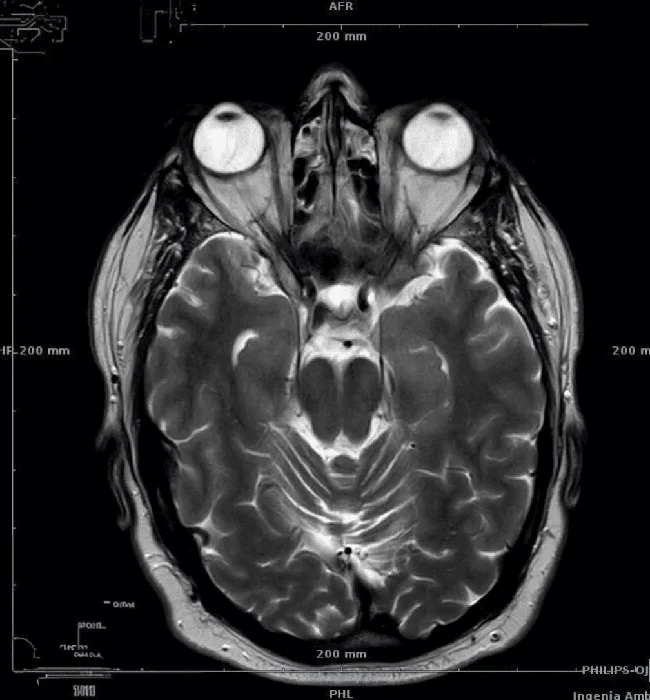

«Левое полушарие моего мозга больше правого»

Технически ваша правая сторона больше. МРТ-сканы делаются снизу, поэтому вы смотрите сверху вниз, а не наоборот.